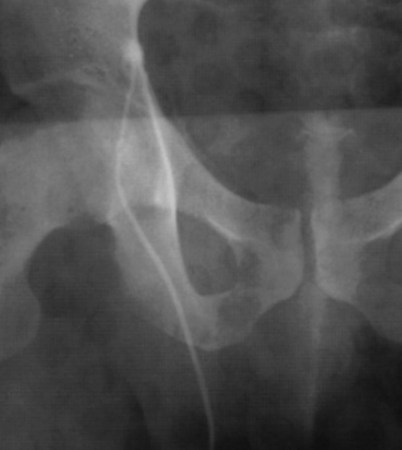

If a large amount of fluid is found in the vasal lumen and microscopic examination reveals the presence of sperm, the obstruction is toward the seminal vesicle end of the vas. In these cases the vas is usually markedly dilated. A 2-0 Proline suture can be passed toward the seminal vesicle end of the vas and a clamp placed on the Proline when the suture passes no farther. This is particularly useful for delineating the site of inguinal obstruction from prior groin surgery. If the obstruction is proximal to the inguinal scar, formal vasography is performed by passing a No. 3 whistle-tip ureteral catheter toward the seminal vesicle end of the vas. A 16-Fr Foley catheter is placed in the bladder, and the balloon is filled with 5 mL of air. Placing the balloon on gentle traction before vasography prevents reflux of contrast into the bladder, which can obscure detail (Fig. 22–5). The air-filled balloon also identifies the location of the bladder neck relative to any obstruction. After the vasa have been cannulated, vasograms are performed with the injection of 0.5 mL of water-soluble contrast media (Fig. 22–6). If vasography reveals obstruction at the site of the ejaculatory ducts (Fig. 22–7), indigo carmine is injected in both vasa to assist a transurethral resection (TUR) of the ejaculatory ducts (see Diagnosis later). If both vasa are visualized after injection of contrast into only one vas (Fig. 22–8), it means both vasa empty into a single cavity, usually a midline ejaculatory duct cyst.